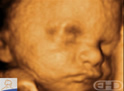

CinemaFrequência Fetal Respiratória |

| Compre AgoraDe The Biology of Prenatal Development. |

Roteiro: Die Atemfrequenz des Fötus kann sich bis zu 44 Ein- und Ausatemzyklen pro Minute steigern. |